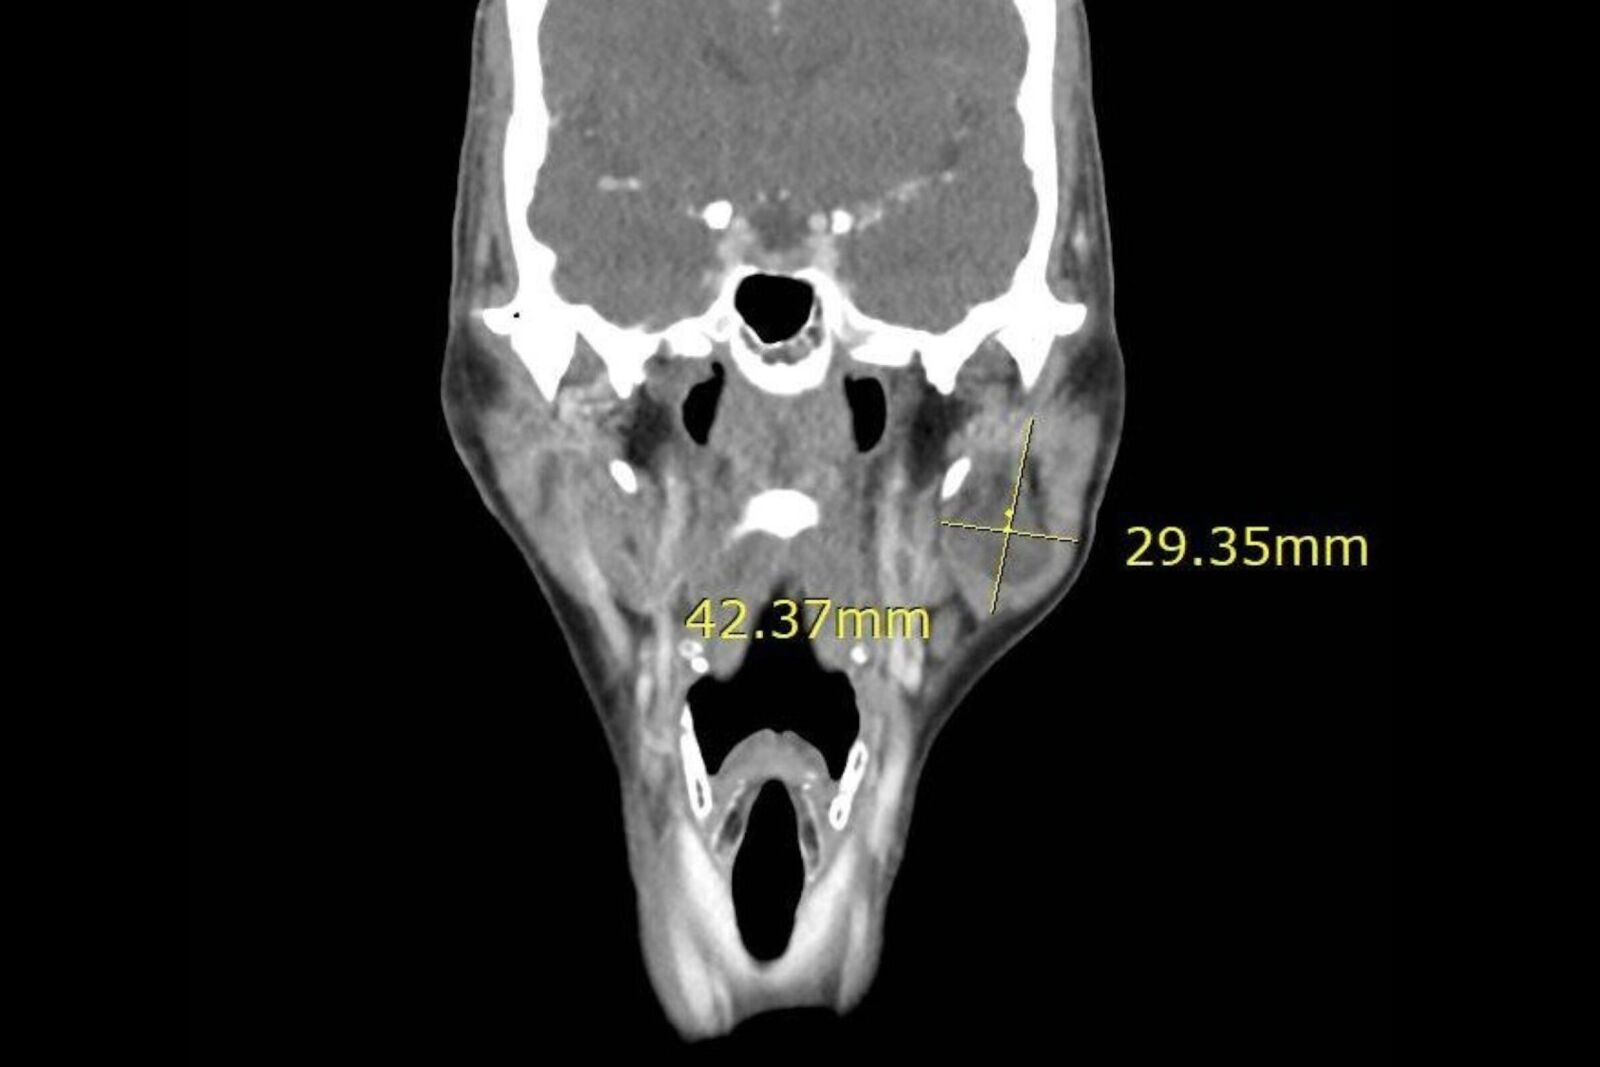

收治病人的台北慈濟醫院耳鼻喉科醫師蔡祐任表示,陳女士就醫時,進一步抽吸及影像學檢查發現為腮腺腫瘤,考量外觀影響及腫瘤有惡性可能,決定透過腮腺切除手術,取出腫瘤及腮腺並利用頸部旋轉皮瓣進行修補。